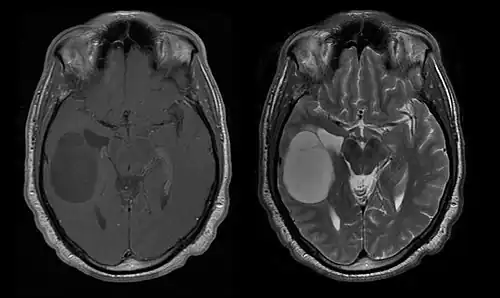

Durch Computertomographie (CT) und Kernspinresonanztomographie (MRT) kann eine Neoplasie im Gehirn effektiv nachgewiesen werden. Zur Identifizierung von Läsionen ist die MRT empfindlicher als die CT, weist aber für Patienten mit Herzschrittmachern, inkompatiblen Prothesen, Metallklammern und anderem Kontraindikationen auf. Die CT bleibt die Methode der Wahl, um Verkalkungen innerhalb der Läsionen oder Knochenerosionen der Schädeldecke oder -basis zu erkennen. Die Verwendung von Kontrastmitteln, die im Fall der CT jodiert und im Fall der MRT paramagnetisch (Gadolinium) sind, ermöglicht die Erfassung von Informationen über die Vaskularisation und Integrität der Blut-Hirn-Schranke, eine bessere Definition der Tumorgeschwulst im Vergleich zum umgebenden Ödem und die Erstellung von Hypothesen über den Grad der Malignität. Die radiologische Untersuchung ermöglicht auch eine Bewertung der mechanischen Auswirkungen und die daraus resultierenden Veränderungen der Gehirnstrukturen, die sich durch den Tumor ergeben, wie zum Beispiel Hydrocephalus und Hernien, deren Auswirkungen tödlich sein können. Schließlich kann mit dieser Diagnostik in Vorbereitung einer Operation der Ort der Läsion oder die Infiltration des Tumors in lebenswichtige Bereiche des Gehirns bestimmt werden. Zu diesem Zweck ist die MRT effizienter als die CT, da sie dreidimensionale Bilder liefern kann.[4]

Diagnostische radiologische Bildgebungsinstrumente heben die Veränderung des neoplastischen Gewebes im Vergleich zum normalen Gehirnparenchym hervor (durch Änderungen der elektronisch dargestellten Dichte des Gewebes bei der CT und der Signalintensität bei der MRT). Wie die meisten pathologischen Gewebe sind auch Tumoren durch eine erhöhte Ansammlung intrazellulären Wassers erkennbar. Im Computertomogramm erscheinen sie hypodens, das heißt von geringerer Dichte als das Gehirnparenchym, im Kernspinresonanztomogramm bei Spin-Gitter-Relaxation hypointens und bei Spin-Spin-Relaxation sowie Protonengewichtung (PD) hyperintens.[5][6]

Auf einer radiologischen Aufnahme sollte der gesunde Gehirnbereich keine besondere Lumineszenz aufweisen. Daher ist es selbstverständlich, dass auf größere Kontrastsignalbereiche geachtet wird.

Im Tumorgewebe ist im Allgemeinen der größere Anteil der Kontrastverstärkung auf die besondere Blut-Tumor-Schranke zurückzuführen, die den Durchgang von Iod (CT) und Gadolinium (MRT) in den intratumoralen extravaskulären Interstitialraum ermöglicht. Dadurch steigt das Signal (Dichte oder Intensität) des Tumors. Es sollte jedoch darauf geachtet werden, dass die Kontrastverstärkung die Neoplasie von Periwundödemen nicht mit Sicherheit abgrenzt. Tatsächlich zeigt der anatomisch-pathologische Befund bei malignen infiltrierenden Gliomen Tumorgewebe, wie zum Beispiel beim Glioblastom und anaplastischem Astrozytom, auch jenseits des vasogenen Ödems, das durch die Zerstörung der Blut-Hirn-Schranke durch den Tumor verursacht wird. Letzterer klinischer Zustand ist durch diagnostische Bildgebung schlecht nachweisbar.[5][6]

Die Computertomographie des Gehirns zeigt typischerweise eine Gewebsmasse, die entweder durch Kontrast verstärkt werden kann. Bei der CT erscheinen niedriggradige Gliome normalerweise isodens zum normalen Parenchym und zeigen daher möglicherweise keine Kontrastverstärkung. In ähnlicher Weise sind Läsionen in der Fossa cranii posterior, der hinteren Schädelgrube, im CT schwer zu identifizieren. Folglich sind die Ergebnisse einer solchen Tomographie allein nicht immer für diagnostische Zwecke ausreichend.[4] In zweifelhaften Fällen ist die Verwendung der empfindlicheren Kernspintomographie unerlässlich.

Auf -Kernspintomogrammen erscheint ein intrakranieller Tumor als massive Läsion, die nach Verwendung des Kontrastmittels lumineszierender werden kann. Eine Signalanomalie gibt es jedoch immer in -Kernspintomogrammen, die auf das Vorhandensein einer Neoplasie oder eines vasogenen Ödems hinweist. Normalerweise ist eine stärkere Lumineszenz (Kontrastverstärkung) ein Hinweis auf einen Tumor höheren Malignitätsgrades. Ein Kontrastring ist charakteristisch für ein Glioblastom, wobei der Lumineszenzanteil dem lebenswichtigen Teil des bösartigen Tumors und der dunklere -hypointense Bereich der Gewebenekrose entspricht.[4]